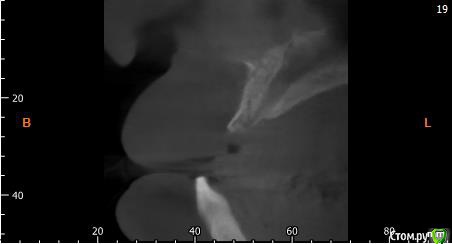

Собственно ситуация такая. Фронтальные зубы сверху были потеряны в результате серьезной травмы,  ! Фактически полное отсутствие костной ткани в области фронтальных зубов и по толщине и по высоте. Пациент ходит с чс протезом и хочет нечто несъемное.

Интересует как лучше это сделать при таких объемных дефектах.  Мои мысли первым этапом сосидж, потом 4 импланта. Но как быть с временным протезированием?